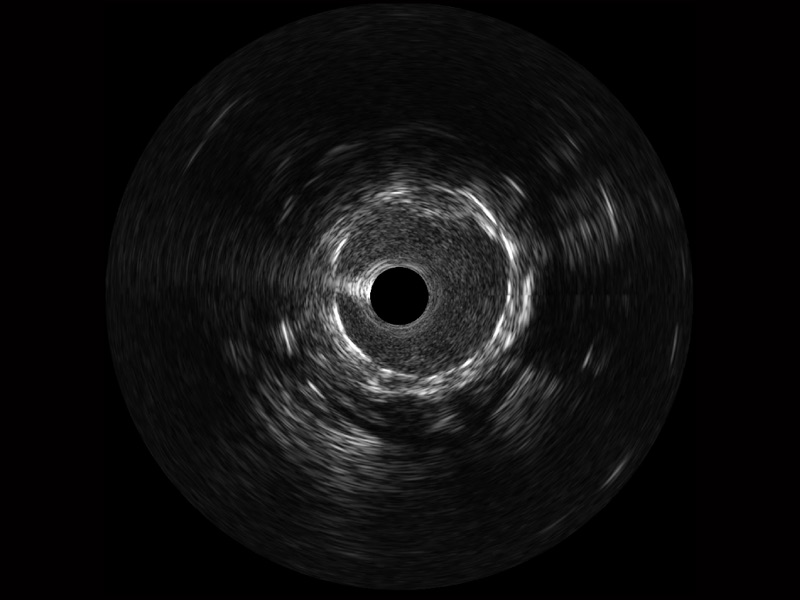

临床图

组织脱垂